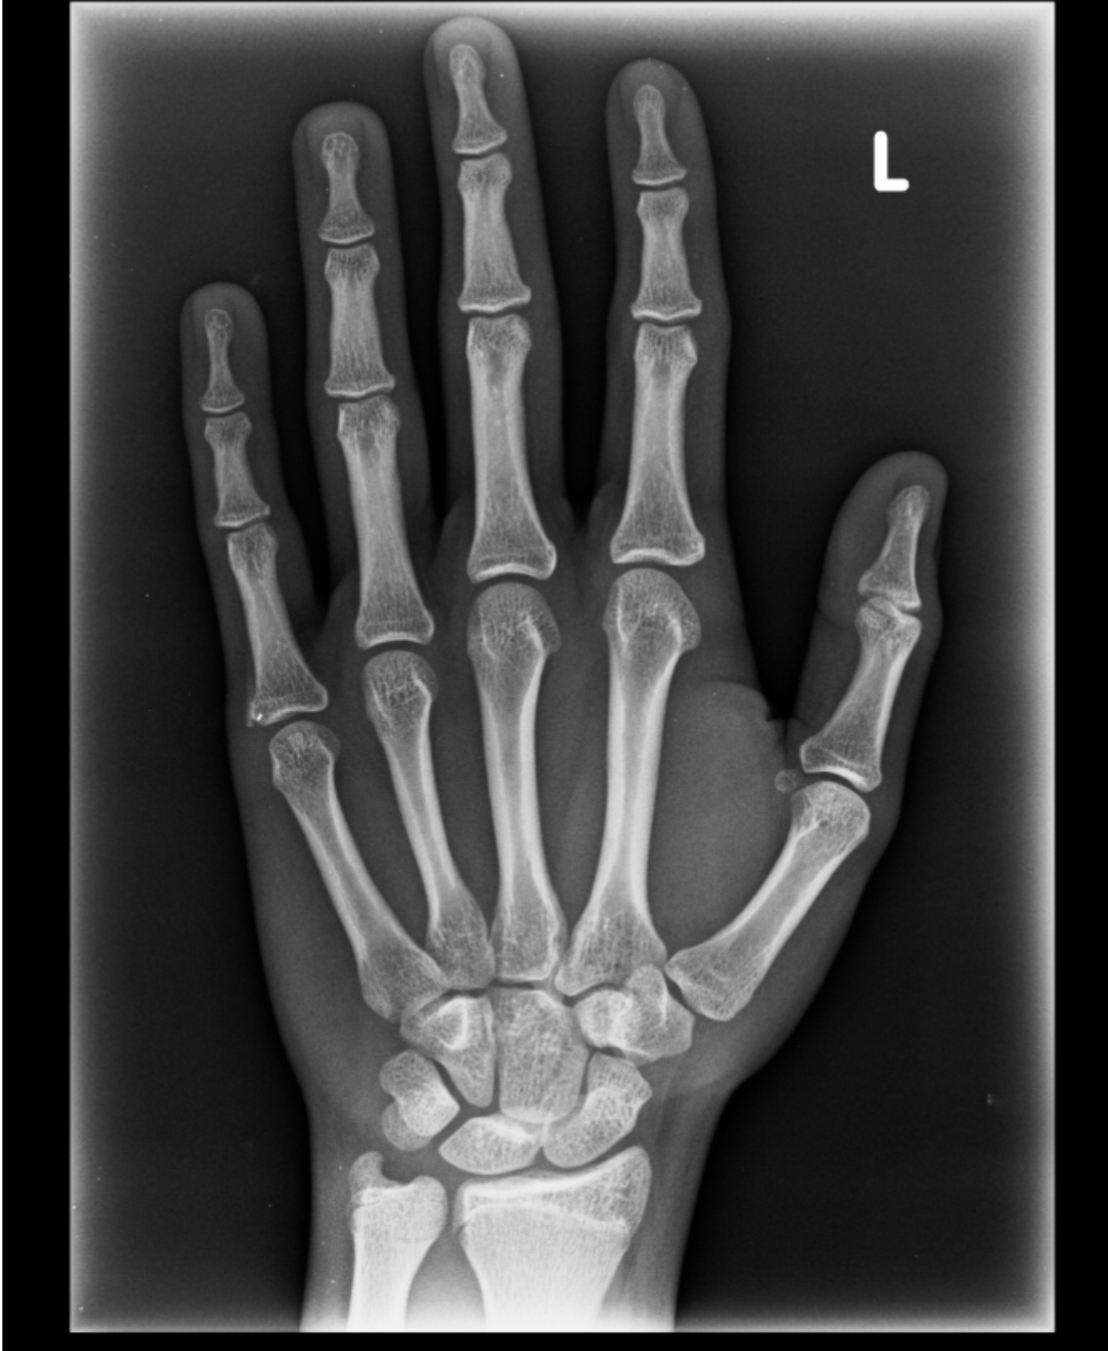

Now I had to go to the doctor and my growth plates are slightly open:

IMG 9736

View attachment 2743726